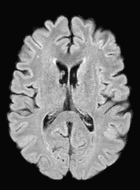

Although ISBI-61 includes longitudinal images, we performed the segmentation in a cross-sectional manner. The segmentations were generated in a similar fashion as the MS-100 dataset (Sec. 4.1) by averaging two memberships obtained using two sets of training. A typical segmentation example is shown in Fig. 7, where the subject has high lesion load (cc).